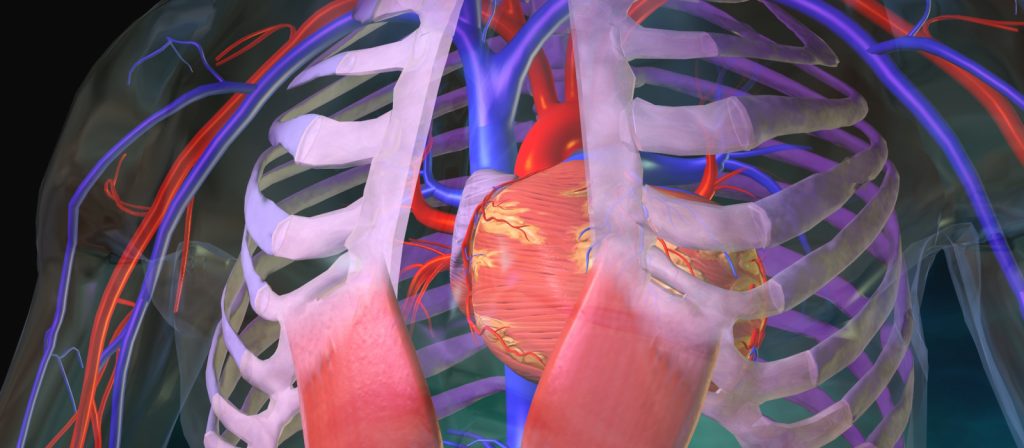

Açık kalp ameliyatı, kalp hastalıklarının tedavisinde yaygın olarak başvurulan bir cerrahi işlemdir. Bu ameliyat, kalp damarlarının açılması, onarılması veya değiştirilmesi için gerçekleştirilir. K

Minimal İnvaziv Kalp Cerrahisi Nedir?Minimal invaziv kalp cerrahisi, geleneksel açık kalp ameliyatlarına göre daha küçük kesilerle yapılan bir tedavi yöntemidir. Bu yöntem, dah